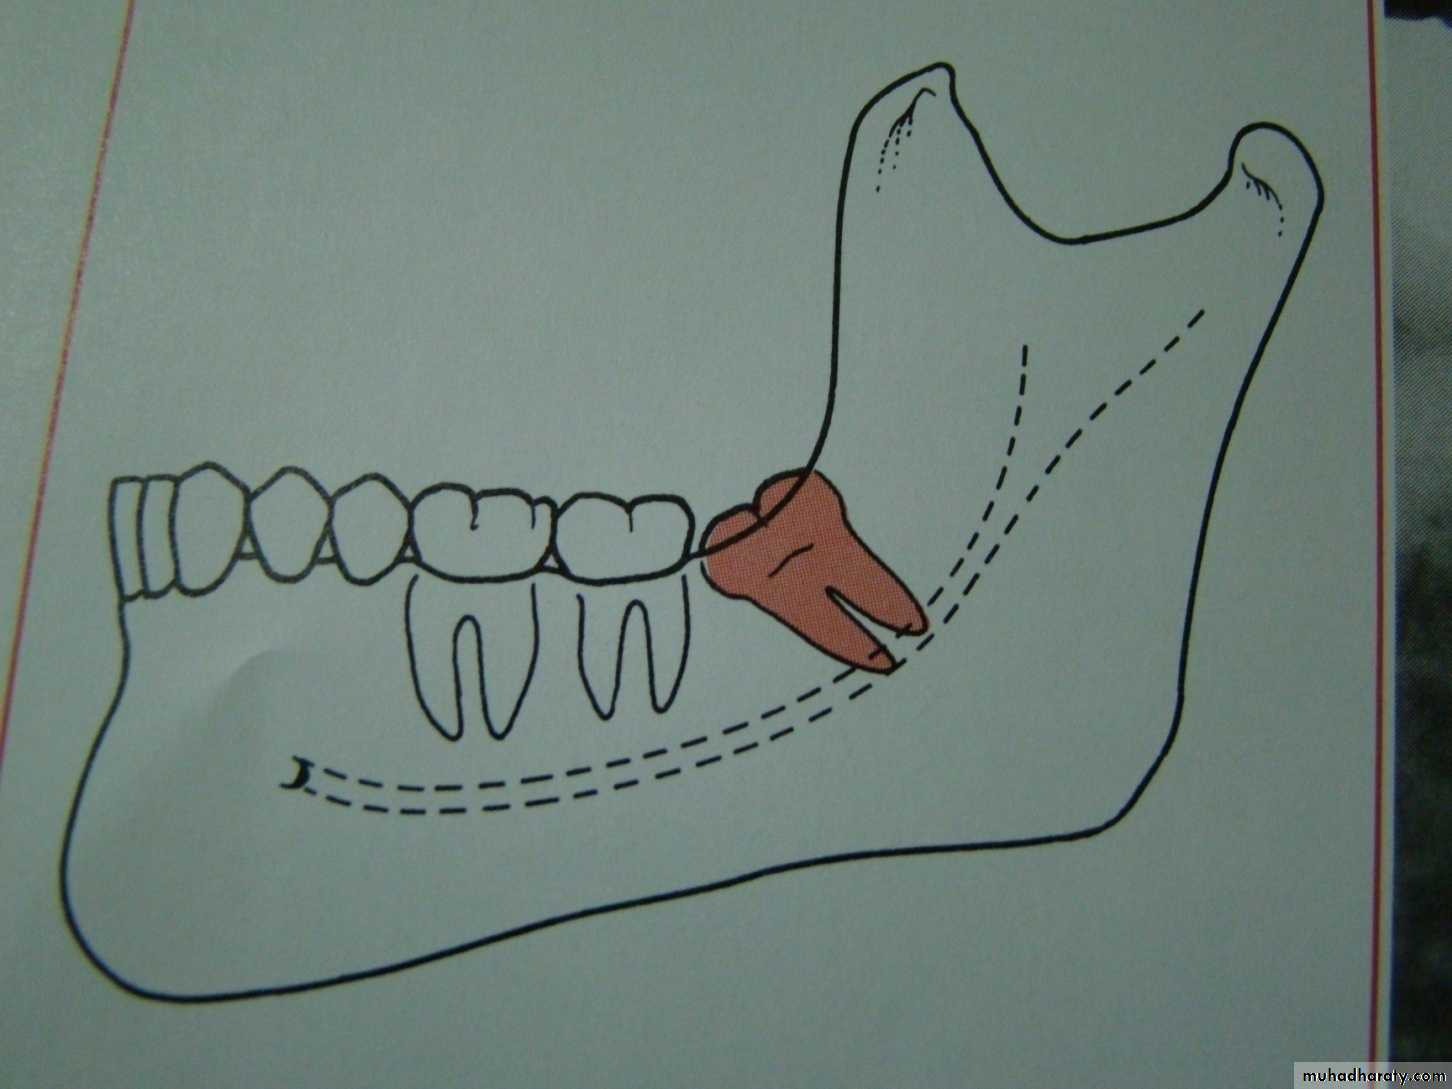

Relation of the impacted tooth to the anterior border of the ramus

Class 1 : the space between the lower second molar and the anterior border of the ramus is sufficient to accommodate the mesio distal dimension of the crown of the impacted lower third molarClass 2 : the space between the lower second molar and the ramus is insufficient to accommodate the crown of the impacted tooth .so part of it in the body and the other part lie in the ramus .

Class 3 the anterior border of the ramus lie near the distal surface of the lower second molar ,so ,the whole impacted tooth lie within the ramus .